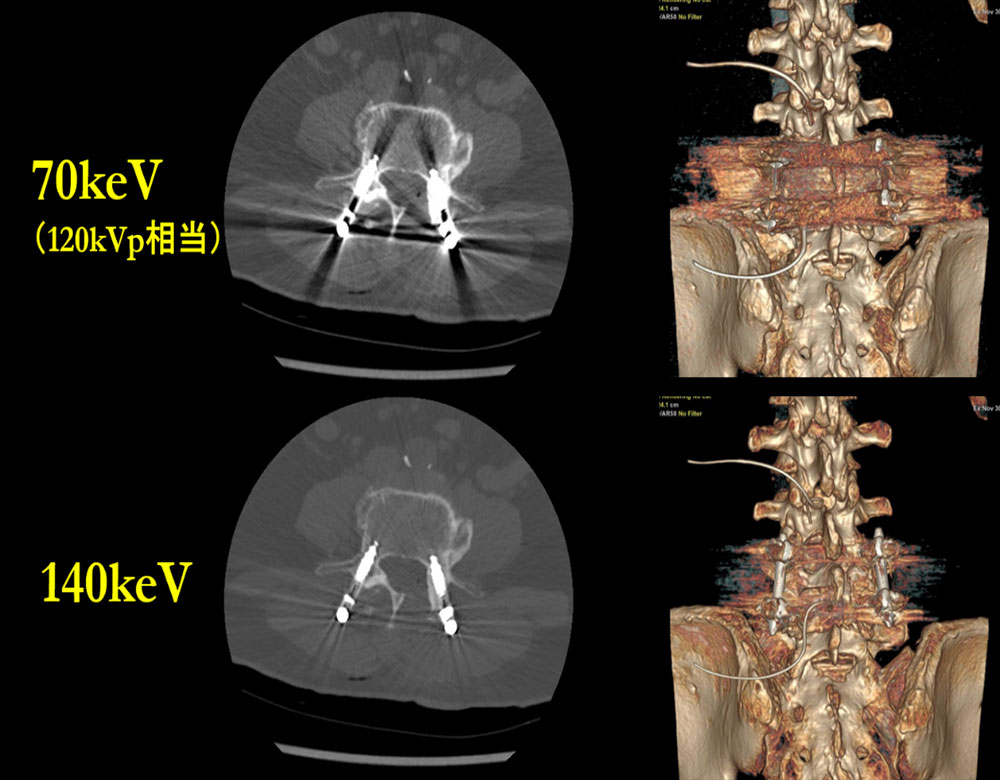

■ 金属アーチファクトの低減

整形領域における術後の体内インプラントはSingle energy CT(以下、SECT)の撮影では、アーチファクトが多く発生し、診断の妨げになることが多々あった。金属アーチファクトの低減はMAR(Metal Artifact Reduction)の再構成で行うことができるが、金属辺縁の形状が変形するというデメリットもある。このデメリットを脊椎外科の医師よりDECTでの撮影で改善できないか依頼があり、撮影する運用に至った。

Fig2のように仮想単色X線画像にて70keVに比べ140keVの画像では、Axial画像・VR画像ともに金属の形状を保ちつつアーチファクトを大きく低減することができ、現在も撮影を適用している。

RevolutionCT_Minamitohoku03.jpg

Fig 2, 金属の形状保持を目的とした

高keVにおける金属アーチファクトの低減